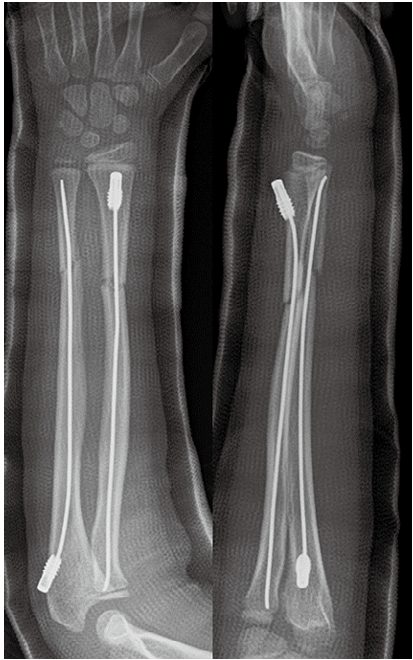

小児前腕骨骨折は日常診療で最も多く遭遇する骨折であり,小児全年齢層の骨折中40%を占めるとされています。

受傷年齢は4〜14歳が多く,受傷機転はほとんどが転倒・転落で,骨折部位は骨幹端,骨端が最も多く,次いで骨幹部骨折が多いです。

小児前腕骨骨折は,年齢,骨折部位,転位の程度や方向,リモデリング能力に応じて治療方針を決定します。

治療成績は一般的に良好ですが,成長障害や再骨折のリスクが高いものもあります。

ずれが少ないものはギプスによる保存治療を行います。4週程度ギプス固定を行うことが多いです。ずれの大きいものは手術となります。

その場合は総合病院へ紹介いたします。